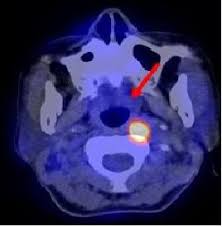

Chụp Positron cắt lớp hay còn gọi là PET hoặc PET-SCAN hay PET/CT là một kỹ thuật chẩn đoán trong chuyên ngảnh Chẩn đoán hình ảnh y học, cho phép đánh giá chức năng sinh học của một số cơ quan nội tạng và chẩn đoán bệnh.

Chụp Positron cắt lớp hay còn gọi là PET hoặc PET-SCAN hay PET/CT là một kỹ thuật chẩn đoán trong chuyên ngảnh Chẩn đoán hình ảnh y học, cho phép đánh giá chức năng sinh học của một số cơ quan nội tạng và chẩn đoán bệnh .

Các kỹ thuật về chẩn đoán khác như chụp CT hay MRI cho chúng ta những hình ảnh về cấu trúc giải phẫu của các tạng. Trong khi đó PET cho chúng ta biết thêm về chức năng chuyển hóa trao đổi chất của các mô và cơ quan vì trong máy có 2 thành phần là CT và PET.

Tất cả các tế bào cần năng lượng để sống và hoạt động. Một trong những nguồn năng lượng ấy là đường. Các tế bào bệnh thường cần nhiều năng lượng hơn và tiêu hao nhiều đường hơn so với các tế bào lành. Đánh giá sự chênh lệch này để chẩn đoán bệnh là nguyên lý hoạt động cơ bản của PET.

Các hợp chất giống như đường (ví dụ gluco FDG) được đánh dấu bằng chất phóng xạ và được tiêm vào cơ thể bệnh nhân. Sau một thời gian (khoảng 60 phút) khi các mô đã hấp thụ các hợp chất đánh dấu thì máy chụp PET sẽ ghi lại tín hiệu phát ra từ chất phóng xạ trong các hợp chất đánh dấu đó. Các tín hiệu sẽ được chuyển thành hình ảnh thông qua một hệ thống máy tính, sau đó các bác sĩ sẽ phân tích hình ảnh để chẩn đoán bệnh. Các vùng bị bệnh trên hình ảnh PET là những vùng tập trung nhiều chất phóng xạ (hay những vùng có nồng độ gluco FDG cao - những vùng nóng) .

Hầu hết các khối u có mức trao đổi chất cao hơn so với các mô lành . Dựa vào độ tập trung gluco FDG chúng ta đánh giá được mức trao đổi chất của các mô, từ đó chẩn đoán được bệnh lý của bệnh nhân.